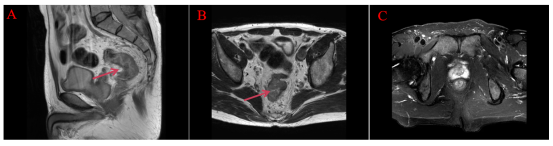

2020.09.23 直肠MRI影像:直肠异常改变,符合直肠Ca。发现直肠癌距肛门位置小于10cm。

image.png

图1 初诊时直肠MRI